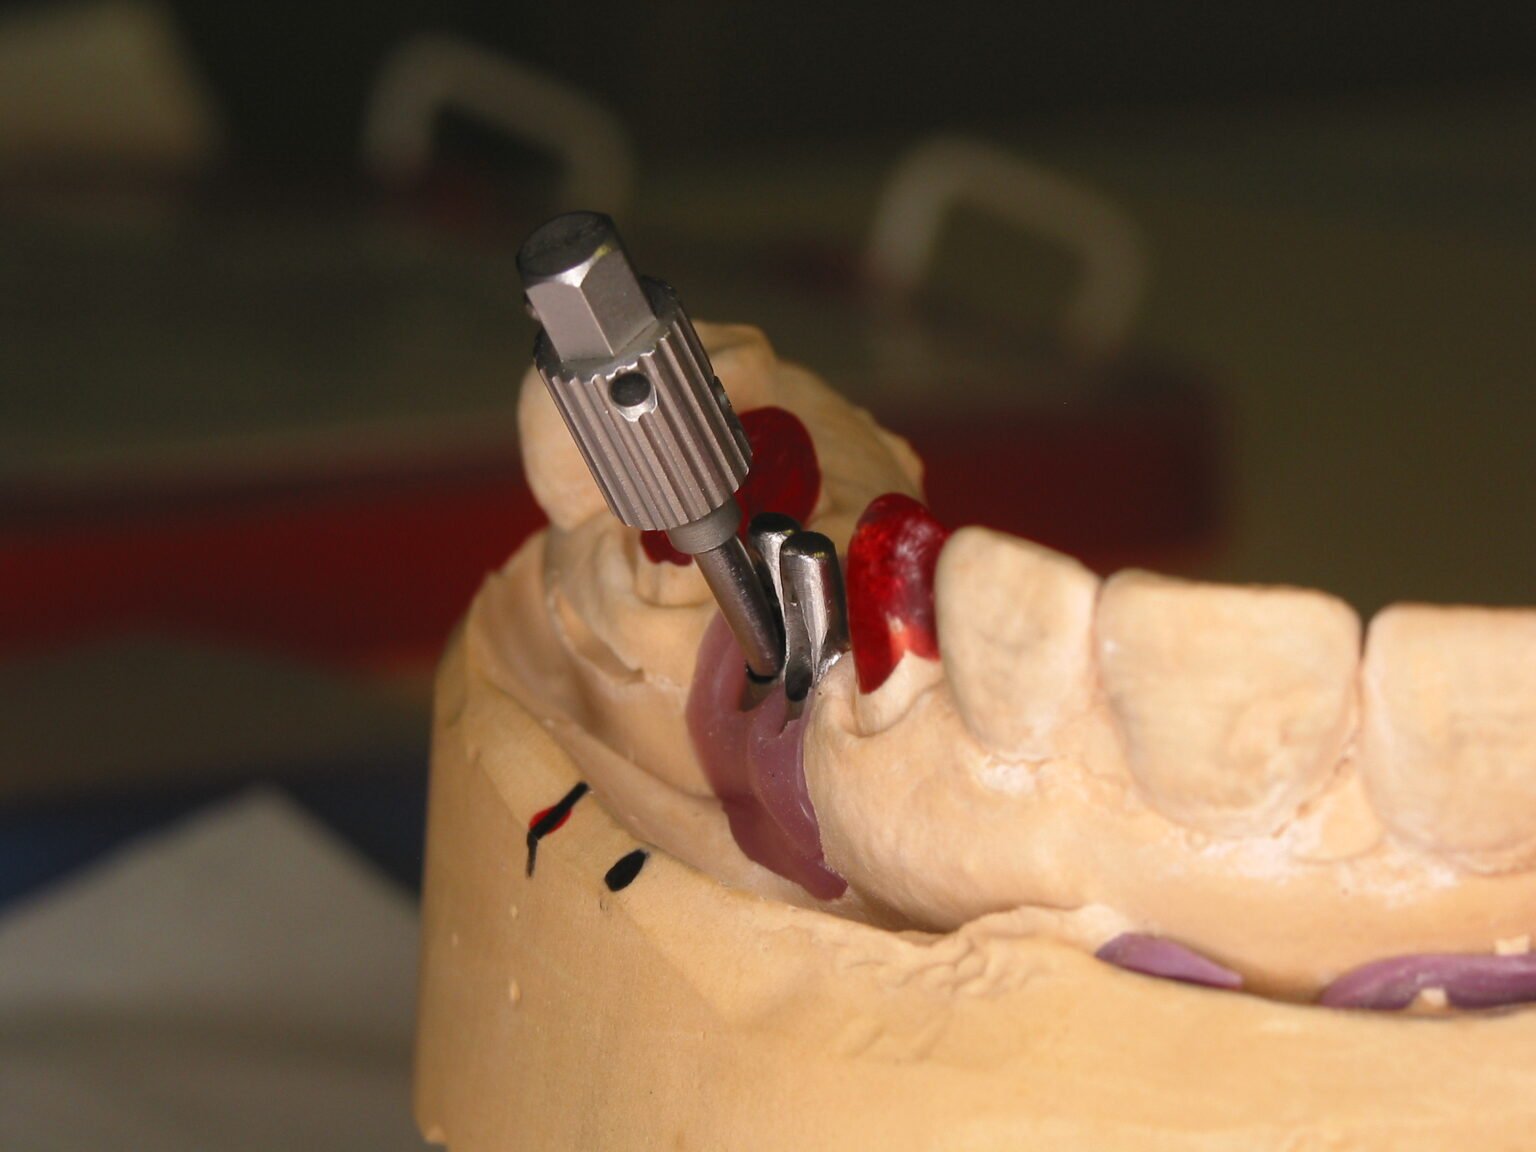

Implantatversorgungen stellen besondere Anforderungen an die Gestaltung von Passung, Kraftführung und Emergenzprofilen. Entscheidend ist dabei, dass alle Komponenten zueinander stimmig aufgebaut sind – von der Implantatplattform über das Abutment bis zur finalen Morphologie.

Ein Schwerpunkt unserer Arbeit liegt auf der kontrollierten Ausformung der Weichgewebsbereiche: Übergänge werden so gestaltet, dass sie Reinigungsfähigkeit, Gewebestabilität und ästhetische Wirkung unterstützen. Auch die Schraubenkanalführung wird bewusst positioniert, um spätere Eingriffe und Versorgungswechsel zu erleichtern.

Bei der Ausarbeitung achten wir darauf, dass Kontaktpunkte und Okklusion chairside nur minimal angepasst werden müssen. Die Materialwahl erfolgt indikationsbezogen – je nach Belastung, Sichtbereich und gewünschtem Transluzenzgrad.